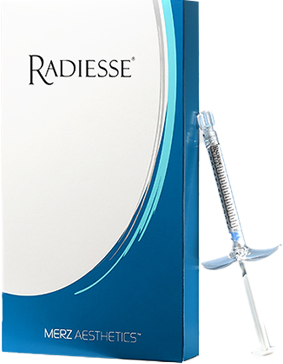

섬유아세포가 대사활동을 하는 동안 섬유아세포에 자극을 주어

콜라겐을 생성하거나, 콜라겐이 서로 합성되는 현상이 일어납니다.

탄력 개선